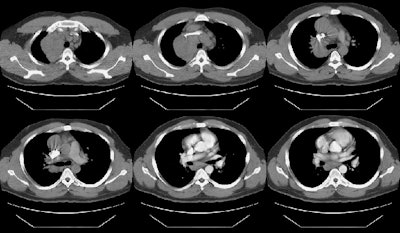

The CT scan demonstrated a large anterior mediastinal/right paratracheal mass which severely compressed the superior vena cava, coupled with mediastinal and subcarinal adenopathy. Mediastinoscopy was performed and the patient was discovered to have Hodgkins lymphoma.